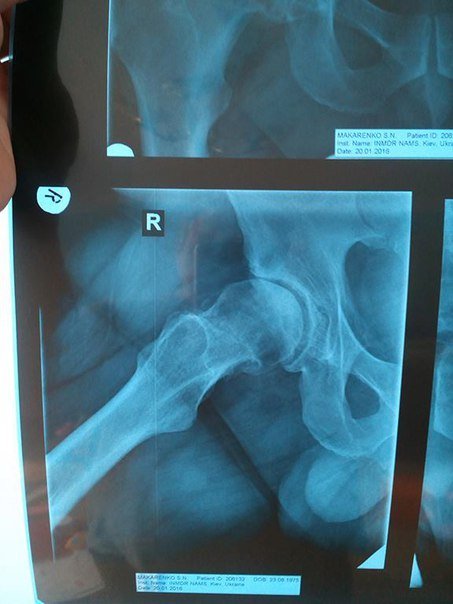

Сергію Макаренко потребує заміни тазобедренного суглоба правої ноги. Операцію робитимуть у Шведсько-українському медичному центрі в Чернівцях. Операція, якісний керамічний протез та двотижнева реабілітація коштують 7500 доларів США.

«З огляду на те, що я маю невеликі доходи у сфері своєї діяльності і значну частину їх з’їдає винаймання житла, сплата комунальних послуг та утримання сім’ї, то вказану суму я буду збирати дуже довго і за цей час я можу взагалі опинитися у інвалідному візку.Багатої та забезпеченої рідні я теж не маю, тож вимушений звертатися до вас друзі. Буду вдячний за будь яку допомогу. Якщо у Вас є контакти, куди можна звернутися по допомогу, теж буду дуже вдячний. Обіцяю документально відзвітувати, якщо вдасться зібрати необхідну суму та зробити операцію, і звітувати кожного тижня про грошові надходження на рахунок. Також додаю рентгенологічні знімки та висновок. Можете порівняти як виглядає мій відносно здоровий суглоб з тим який треба протезувати. Знімок R, це той який потрібно протезувати», – пише на своїй сторінці у мережі Сергій Макаренко.